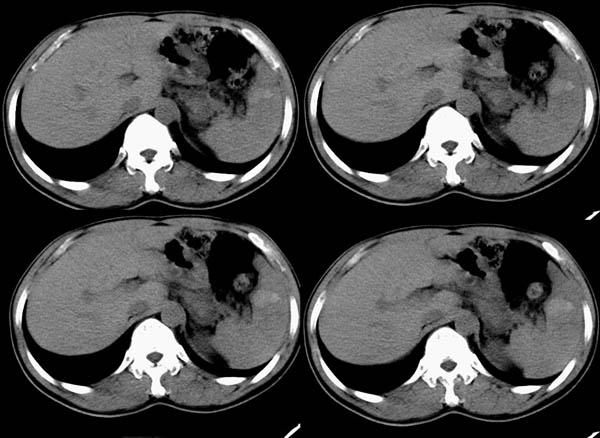

m50y以腹疼、腹胀2小时就诊。腹透肠胀气较明显,余无明显异常。做ct时腹疼已明显缓解;病人否认外伤史,否认血液病变、否认肝炎史。建议第二天做ct增强,病人第二天放弃了增强。脾脏区较高密度影ct值为60hu,正常脾脏ct值为45hu(窗宽:150,窗位:56)。

脾区病变局部2mm重建:

ct表现:脾脏内见较高密度影ct值为60hu,正常脾脏ct值为45hu(窗宽:150,窗位:56)。 边界清晰,周围见略低密度影

脾脏实质内高密度病变,ct值为60hu,边界清晰,无明显外伤病史,腹痛、腹胀2小时就诊,首先考虑脾脏血管瘤破裂出血。